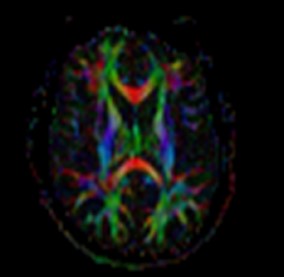

トラクトグラフィ

トラクトグラフィとは白質神経線維の走行方向を可視化したものです。脳神経外科の術前評価に役立ちます。

カラーマップ トラクトグラフィ